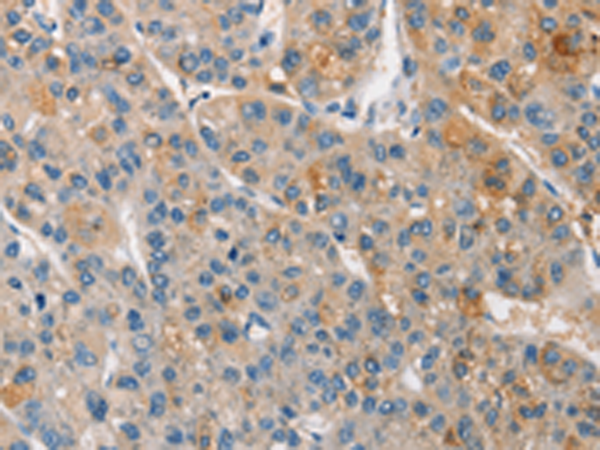

分类: 科研抗体货号: P11195别名: APO-CIV; APOC-IV应用: IHC反应种属: Human